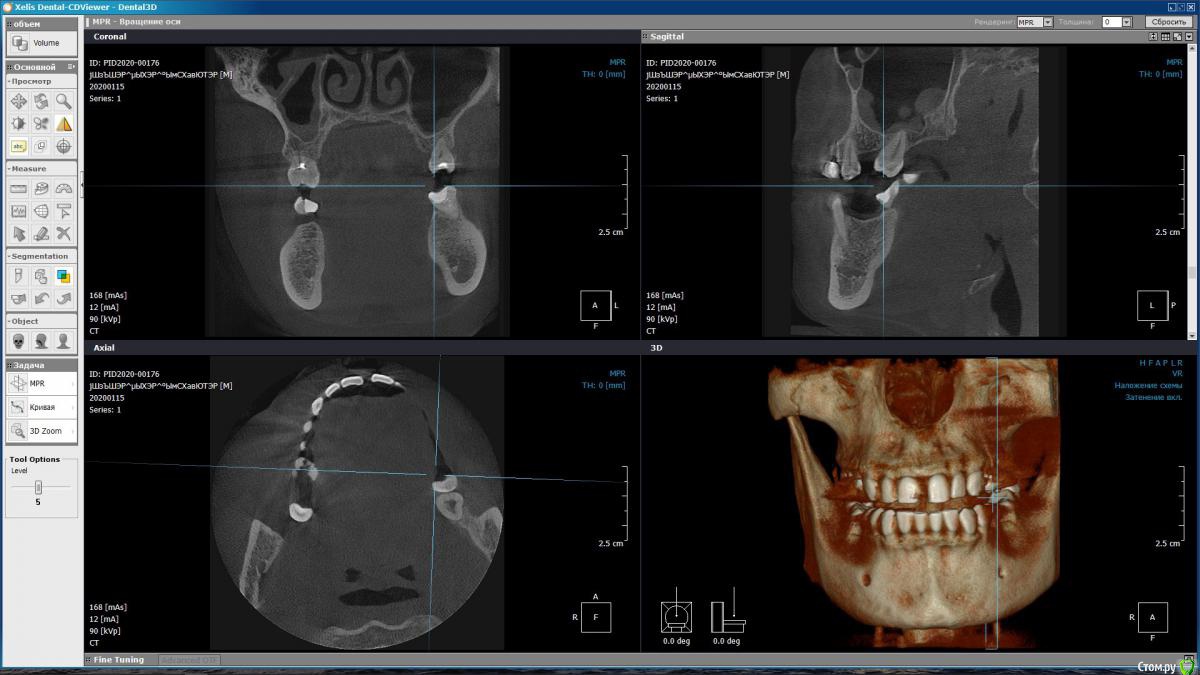

m-e-a Опубликовано 19 января, 2020 Автор Поделиться Опубликовано 19 января, 2020 (изменено) Сделала срезы как смогла, не умею я смотреть КТ Изменено 19 января, 2020 пользователем m-e-a Ссылка на комментарий

red_butler Опубликовано 19 января, 2020 Поделиться Опубликовано 19 января, 2020 На представленных срезах, показаний к удалению не увидел. Нужно смотреть очно и «крутить» Кт Ссылка на комментарий